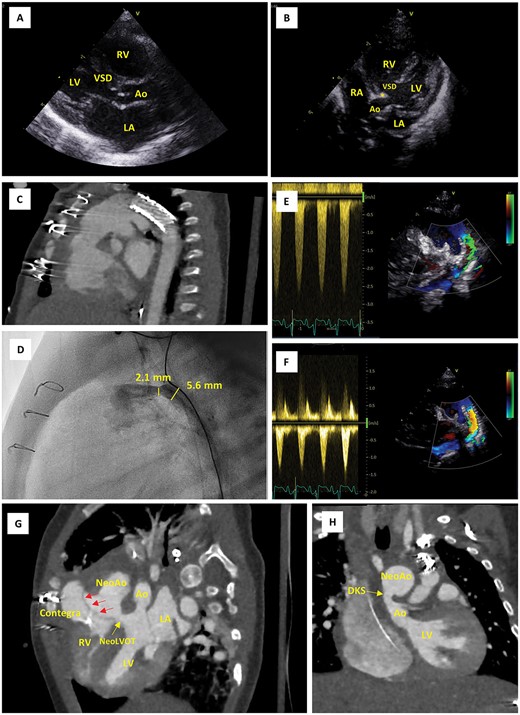

A female newborn, delivered at 39 weeks and 3 days’ gestational age (birth weight 3.4 kg), was admitted to the neonatal intensive care unit (NICU) of our tertiary referral center for planned postnatal care (Table 1). Amniocentesis had revealed 22q11.2 microdeletion and fetal echocardiography allowed for prenatal diagnosis of IAA type B and large inlet VSD with extension to the outlet and posterior displacement of the conal septum resulting in LVOTO. Prostaglandin E1 infusion was immediately instituted. Echocardiography at this point revealed a small, oval shaped LVOT with dimensions 5.0 × 3.7 mm (Fig. 1A and B). The VSD measured 9 mm, whereas the diameters of the aortic valve annulus, sinus of Valsalva and sinotubular junction were 5.2 mm (Z-score − 3.1), 7.6 mm (Z-score − 2.5) and 6.3 mm (Z-score − 1.7), respectively [8]. In addition, the diagnosis of an aberrant right subclavian artery (arteria lusoria) was made, thus indicating IAA type B2.

Imaging findings. (A) Parasternal long-axis echo view on postnatal Day 0, showing the large VSD and narrow native LVOT (5.0 mm in this view). (B) Apical five chamber echo view on postnatal Day 0, showing posterior displacement of the conal septum (*) and the narrow native LVOT (3.7 mm in this view). (C) CTA scans after first cardiac catheterization at the age of 12 days, showing position of the ductal stent. (D) Emergency cardiac catheterization at the age of 2 months, showing restenosis of the (non-stented part of the) proximal duct (30 mmHg, diameter 2.1 mm). (E, F) Pulsed wave Doppler evaluation of ductal flow, showing flow acceleration up to 2.5 m/s when the patient was stabilized at the PICU prior to emergency cardiac catheterization (E) and reduction of this flow acceleration to <1.5 m/s following resolution of the stenosis using a Formula 535 vascular balloon-expandable stent (F). (G, H) CTA scan after Yasui procedure; modified views to demonstrate the Rastelli tunnel (red arrows) and the narrow native aortic valve (Ao) (G) as well as the DKS anastomosis (H). Ao, aorta; CTA, computerized tomography angiography; DKS, Damus–Kaye–Stansel; LA, left atrium; LV, left ventricle; PICU, pediatric intensive care unit; NeoAo, neo-aorta; RA, right atrium; RV, right ventricle; VSD, ventricular septal defect.

During a multidisciplinary meeting the decision was made to pursue initial hybrid palliation consisting of PAB and ductal stenting, followed by delayed biventricular repair using a Yasui-type operation. This strategy would avoid high-risk neonatal surgery and in the meantime allow for potential growth of the LVOT. Ductal stenting was completed at the age of 12 days. A sinus-SuperFlex-DS stent was positioned in the arterial duct using a soft coronary wire (Fig. 1C). The procedure was uncomplicated and the patient could be discharged home at the age of 23 days.